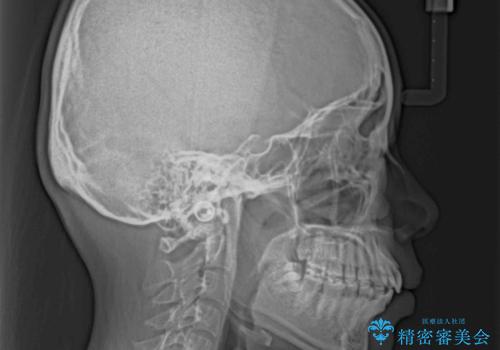

- 出っ歯と口の閉じにくさ、デコボコを気にして来院された患者様です。

口元の突出感を改善するため、上下左右第一小臼歯4本の抜歯を行い、ワイヤー装置による矯正治療を行うこととしました。

抜歯矯正を行ったことで、顎先のつっぱり感や口元の閉じにくさを解消することができました。